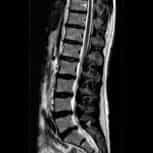

A nossa orientação médica é gratuita para casos de DOENÇA DO FILUM e de patologias que fazem parte dela: a Síndrome de Arnold-Chiari I, a Escoliose idiopática, a Siringomielia idiopática, a Platibasia, a Invaginação Basilar, a Retroflexão do Odontóide e a Angulação do Tronco Cerebral.

Síndrome de Arnold Chiari I,

Escoliose e Siringomielia idiopáticas.